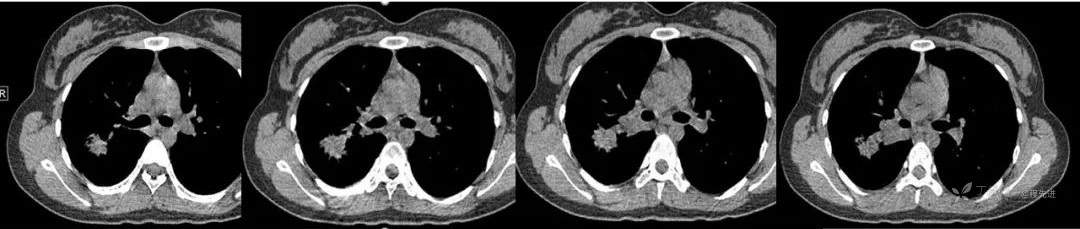

CT 平扫CT值约40HU 增强CT值约80HU

抗结核治疗后,复查